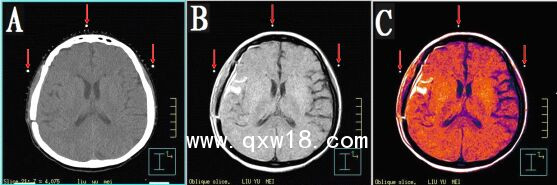

本產(chǎn)品主要適用于不同模態(tài)圖像引導下放療時定位,定點經(jīng)皮穿刺活檢或積液抽吸引流,不同模態(tài)間圖像融合控制點配準等。

3.??同一定位貼,在多種模態(tài)掃描下成像均能顯示為點狀,可用作圖像融合的共同配準控制點,大小、位置一致,方便全身或軀段臟器異機圖像融合,精度高,易開展新的臨床應用。

CT和MR通用型:具有同一個定位球在CT掃描高密度、MR常規(guī)掃描高信號的特點,主要用于

CT/MR圖像融合,更換掃描設備,不需要更換標記點。型號MK⊙CT/MR,每盒三貼;